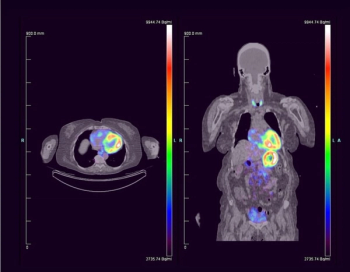

Examining six comparative studies within a new meta-analysis, researchers found that FAPI PET/CT offered 11 percent higher pooled sensitivity and 28 percent higher pooled specificity than FDG PET/CT for diagnosing lymph node metastases in patients with lung cancer.